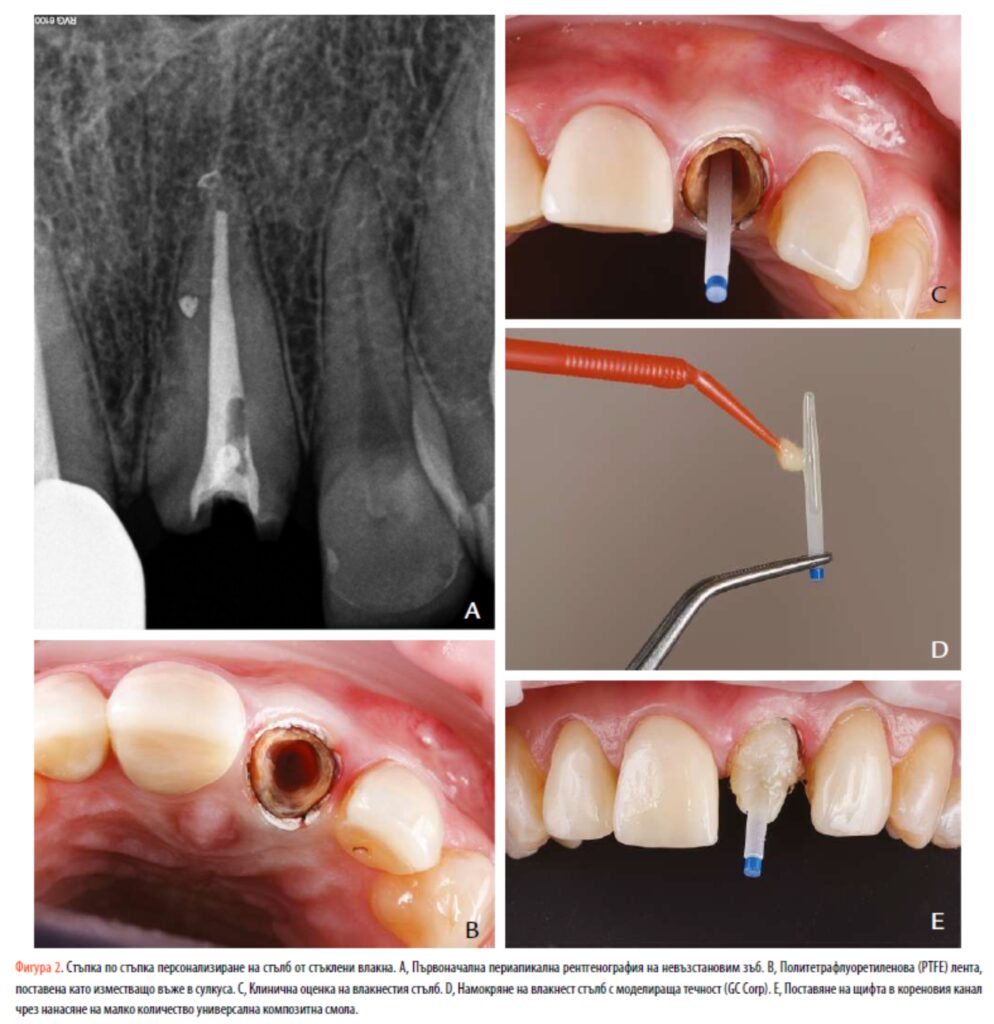

Жена на 55 години е насочена към частна практика за лечение на максиларен ляв централен резец. Тя съобщава за множество разлепвания на циркониева коронка върху зъба (фиг. 1A). Нейната медицинска история не е свързана със съпътстващи заболявания и тя не е била пушач. Останалият зъб имаше субгингивална кариозна лезия и недостатъчна ферула (фиг. 1B). Патологична подвижност не се наблюдава, а дълбочината на сондиране варира между 1,5 и 2 mm. Зъбът беше асимптоматичен при перкусия и палпация, а гингивалния ръб на зъба беше на същото ниво като максиларния десен централен резец. Ендодонтско повторно лечение не беше необходимо въпреки възможното коронарно изтичане, тъй като рентгенографското изследване показа добре обтуриран коренов канал и липса на периапикална лезия (фиг. 2А).

След обсъждане на различни възможности за лечение беше планиран интердисциплинарен подход, базиран на принудителна ортодонтска

екструзия. При локална анестезия кариозният дентин беше отстранен с борер от волфрамов карбид (H1.204.014; Komet). Оперативното поле беше изолирано с помощта на бариера (OptraDam; Ivoclar AG) и политетрафлуороетиленова (PTFE) лента, поставена като изместваща връв в сулкуса (фиг. 2B). Оптичен стълб (Blue X-Post #3; Dentsply Sirona) беше маркиран, намален до подходяща дължина с високоскоростен диамантен ротационен инструмент при водно охлаждане и абразиран с въздушни частици (AquaCare TWIN; Velopex) с 29 mm частици алуминиев оксид (Al2O3) (AquaAbrasion; Velopex) за 5 секунди (фиг. 2C). Частиците бяха отстранени с въздушна спринцовка за 5 секунди и повърхността на стълба беше почистена с 95% изопропилов алкохол и намокрена с моделираща течност (GC Corp) (фиг. 2D). Слой от глицеринов гел (K-Y лубрикантен гел; Johnson & Johnson) беше поставен вътре в кореновия канал, за да се предотврати или предотврати задържането на индивидуализирания кол с композит (Ceram.x Spectra ST. LV-A2; Dentsply Sirona). След 10-секунден цикъл на светлинна полимеризация (SmartLite Pro; Dentsply Sirona), щифтът беше отстранен и полимеризацията на композита беше завършена извън устата (фиг. 2E, 3A). Стените на дентина на кореновия канал бяха абразирани с въздушни частици за още 10 секунди с 50-mmA2lO3 (AquaCare; Velopex) и след това почистени с вода за 20 секунди. Коренните стени бяха изсушени с абсорбиращи хартиени върхове преди свързване. Prime&Bond active (Dentsply Sirona) в режим на самоецване със Self Cure Activator (Dentsply Sirona) беше приложен вътре в стените на кореновия канал за 20 секунди. Излишъкът от адхезив се отстранява с абсорбиращи хартиени накрайници и разтворителят се изпарява чрез лек въздушен поток за 5 секунди. Повърхността на композитната смола на щифта след това се активира повторно със същия протокол, използван преди, но замествайки композитната смола с адхезива за дентин, нанесен върху зъба. Циментирането на влакнест щифт и изграждането на сърцевината бяха извършени в 1 стъпка чрез нанасяне на двойно полимеризираща композитна смола (Core-X Flow; Dentsply Sirona) директно върху повърхността на влакнестия щифт и в кореновия канал (фиг. 3B-H).